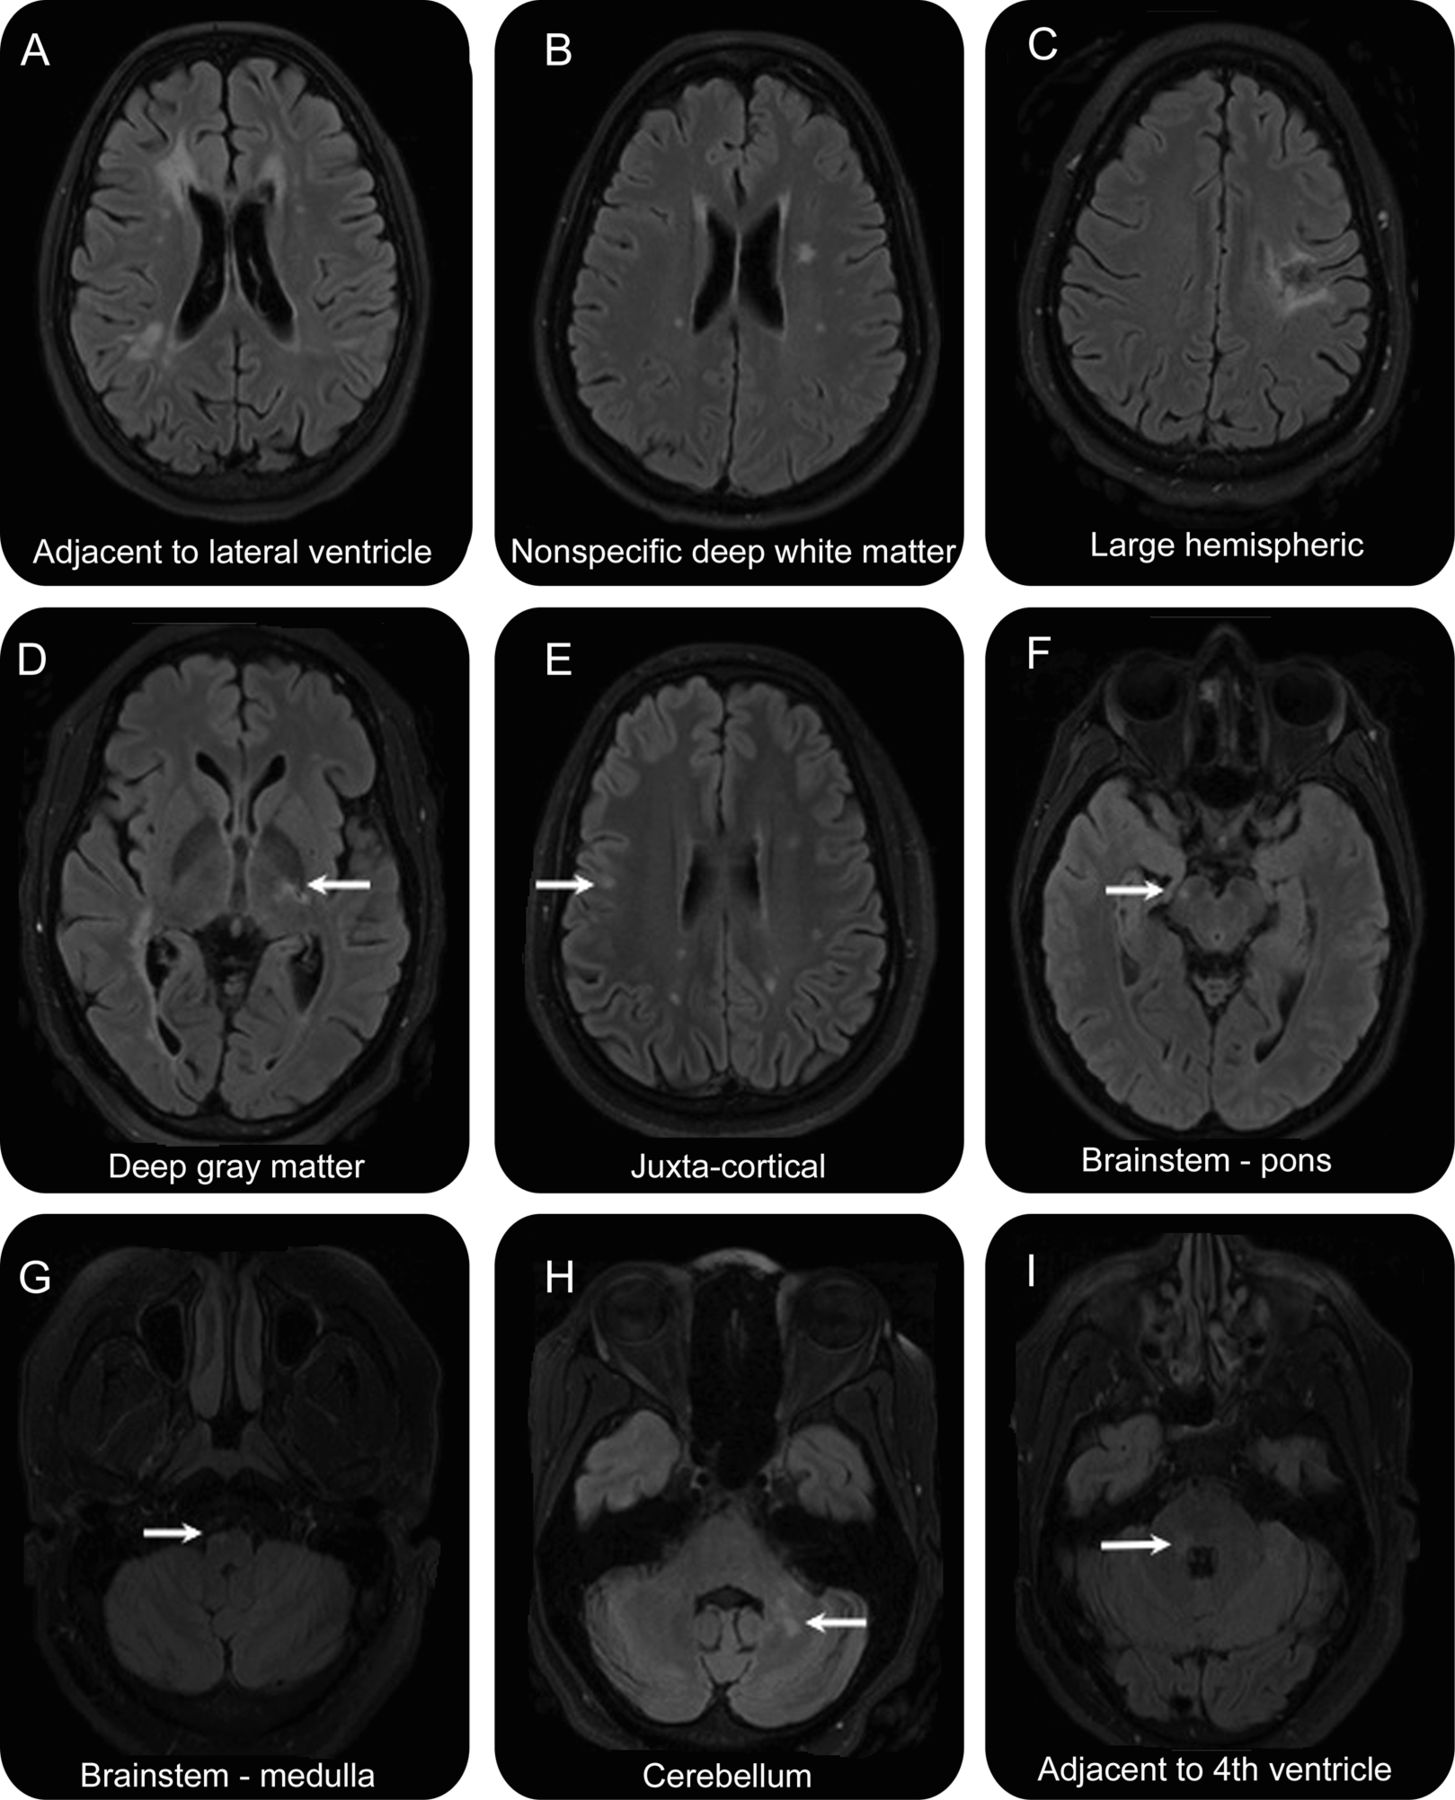

的比例NMOSD T2损伤发生在大脑中的特定空间位置所示表2。这些模式所示的例子图2。值得注意的是,患者最常见的分布NMOSD幕上的深白质病变。

的例子NMOSD(所有积极的aquaporin-4抗体)fluid-attenuated反转恢复扫描显示病变位置对应表2。(一)邻近侧脑室。(B)特异性的白质。(C)大半球病变的检查。(D)丘脑。Juxtacortical (E)。(F)桥的。(G) Medullar延髓。小脑(H)。(我)毗邻第四脑室。

七位26 NMOSD患者大脑病变,或15.9%的患者NMOSD,满足Barkhof标准名RRMS病变的传播空间,17基于unenhanced大脑核磁共振。有重要的区别,然而,在病变的形态。没有患者NMOSD与形态学juxtacortical T2 hyperintensities暗示U-fiber位置,与名RRMS队列。也注意损伤邻近侧脑室的NMOSD往往位于前部和后部角(图2一个),没有患者卵圆形病变在垂直对齐(道森的手指)。